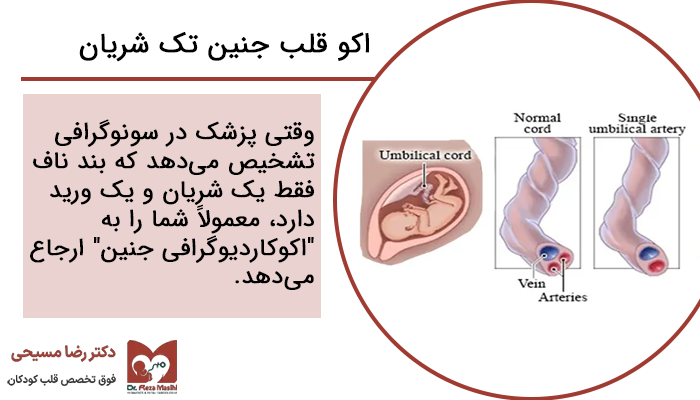

وقتی پزشک در سونوگرافی تشخیص میدهد که بند ناف فقط یک شریان و یک ورید دارد (بهجای دو شریان و یک ورید که حالت طبیعی هست)، معمولاً شما را به سونوگرافی دقیقتر به نام ” اکو قلب جنین“ ارجاع میدهد.